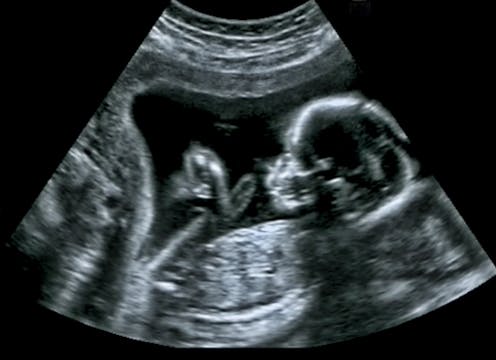

Neural tube defects are defects of the central nervous system that occur in the first month of an embryo’s life. They include conditions such as spina bifida, where the spinal column doesn’t close properly, and anencephaly, a condition where large parts of a baby’s brain and skull are missing. The incidence of neural-tube-defect pregnancies in the UK is around 13 per 10,000 births.